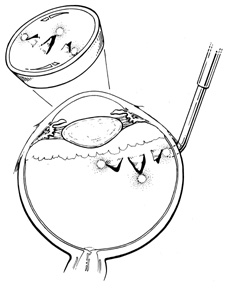

One result of circumferential encircling scleral buckles is fish-mouthing of retinal breaks.72,73 This is caused by the relative circumferential shortening of the sclera and choroid induced by the buckle in relation to the retina. This relative excess of retinal surface causes the retina to lie in radial folds over the buckle. These folds, in conjunction with vitreous traction, can result in the failure of retinal breaks to settle over the buckle. The breaks may form an elongated oval configuration in the anteroposterior meridian over the buckle, resembling the open mouth of a fish (Fig. 23). Persistent elevation of the retina resulting from the fishmouth phenomenon can result in surgical failure and therefore needs to be addressed.

Fig. 23. Fishmouth appearance after circumferential buckle.

There are three basic techniques in the management of fishmouth retinal tears. The easiest is to decrease the height of the circumferential buckle. This usually is effective only if buckle height is excessive. Placement of a radial element beneath the circumferential element effectively closes most fishmouth tears.69 The radial element increases the surface area of the pigment epithelium and choroid beneath the break, thereby decreasing the disparity between the retinal surface area and the surface area of the bed of the buckle (Fig. 24). 73 Injection of an intravitreal gas bubble, combined with appropriate positioning, also effectively closes fishmouth tears. The gas is injected through the pars plana under direct visualization with the indirect ophthalmoscope. During the injection, care must be taken to avoid formation of multiple small bubbles, which may then pass through the tear into the subretinal space. This can be prevented by injecting into the most superior aspect of the vitreous cavity. With accurate positioning, a bubble of 0.3 mL is adequate to close retinal breaks of up to one clock hour.74 The use of expansile gases, such as sulfur hexafluoride or perfluoropropane, can increase the intraocular volume of gas.

Fig. 24. Radial element beneath tear alleviating fishmouth phenomenon.